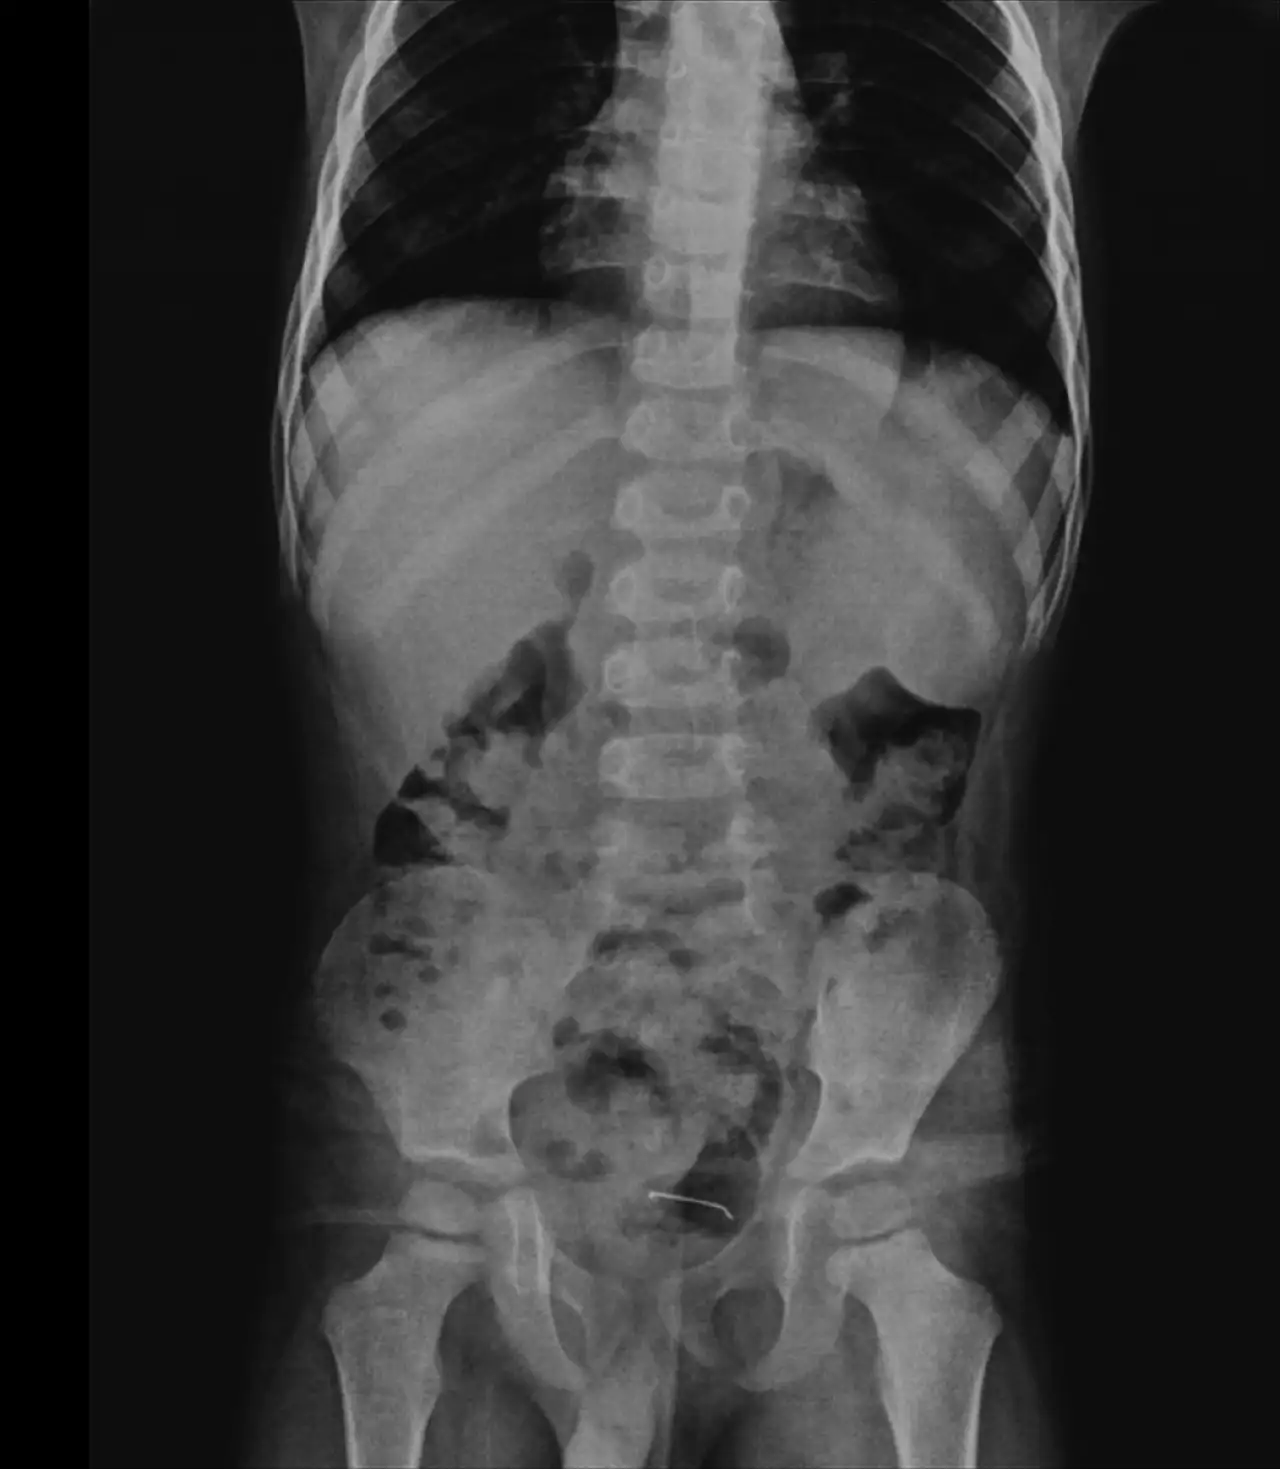

Daha önce farklı sağlık kuruluşlarına başvuran ancak kesin bir sonuca ulaşamayan aile, çocuğun karın ağrısı şikayetinin artması üzerine 4 gün önce Tatvan Devlet Hastanesi’ne başvurdu. Yapılan röntgen incelemelerinde, çocuğun mesane duvarında metal bir cisim bulunduğu tespit edildi. Yaklaşık 3 santimetre uzunluğundaki toplu iğnenin, uzun süre vücutta kalması nedeniyle mesane duvarına yapıştığı belirlendi.

Aileye bilgi verilmesinin ardından Çocuk Cerrahi Uzmanı Op. Dr. Tahsin Onat Kamçı tarafından gerçekleştirilen operasyonla toplu iğne başarılı bir şekilde çıkarıldı.Bitlis'te 5 yaşındaki çocuğun yuttuğu toplu iğne ameliyatla çıkarıldı

Ameliyatı gerçekleştiren Op. Dr. Tahsin Onat Kamçı, çocuğun 9 ay önce bir cisim yuttuğunu ancak ailenin bunun tam olarak ne olduğunu ayırt edemediğini belirtti. Yapılan muayeneler sonucunda, yutulan cismin doğal yollarla vücuttan atılamadığını fark ettiklerini dile getiren Kamçı, şu açıklamalarda bulundu:

"Ameliyat sırasında cismin mesane duvarına yapıştığını tespit ettik ve cerrahi müdahaleyle çıkardık. Operasyon sonrası hastamızı birkaç gün gözlem altında tuttuk. Genel sağlık durumu iyi olan çocuğumuzu taburcu ettik."